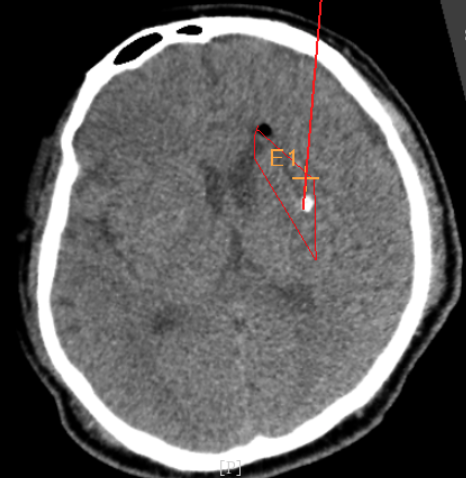

手術(shù)日當(dāng)天,醫(yī)生團(tuán)隊(duì)通過手術(shù)計(jì)劃系統(tǒng)為患者制定手術(shù)靶點(diǎn)及最安全的入顱路徑,隨后將手術(shù)規(guī)劃導(dǎo)入手術(shù)室的機(jī)器人當(dāng)中。

實(shí)際手術(shù)時(shí),機(jī)器人在幾分鐘內(nèi)就完成了空間注冊,機(jī)械臂在定位儀的引導(dǎo)下自動定位,準(zhǔn)確鎖定靶點(diǎn)。

韓帥醫(yī)生借助機(jī)器人操作平臺順利抽出血性液體15ml,與術(shù)前軟件計(jì)算的血腫量完全一致,手術(shù)在30分鐘內(nèi)順利完成。